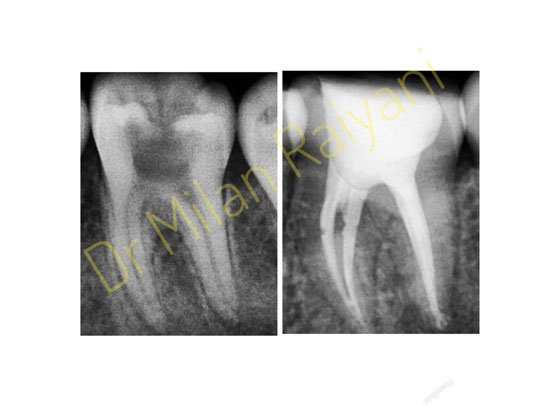

GALLERY